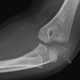

Displaced elbow fat pad

The elbow is the visible joint between the upper and lower parts of the arm. It includes prominent landmarks such as the olecranon, the elbow pit, the lateral and medial epicondyles, and the elbow joint. [Source: Wikipedia ]